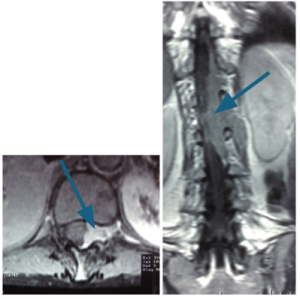

Prueba de elección para tumores de columna y médula espinal. Evalúa partes blandas, relación con la médula y raíces, y detecta compresión, edema, necrosis o hemorragia intratumoral.